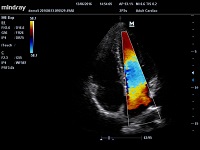

Клинические изображения Mindray M5 new